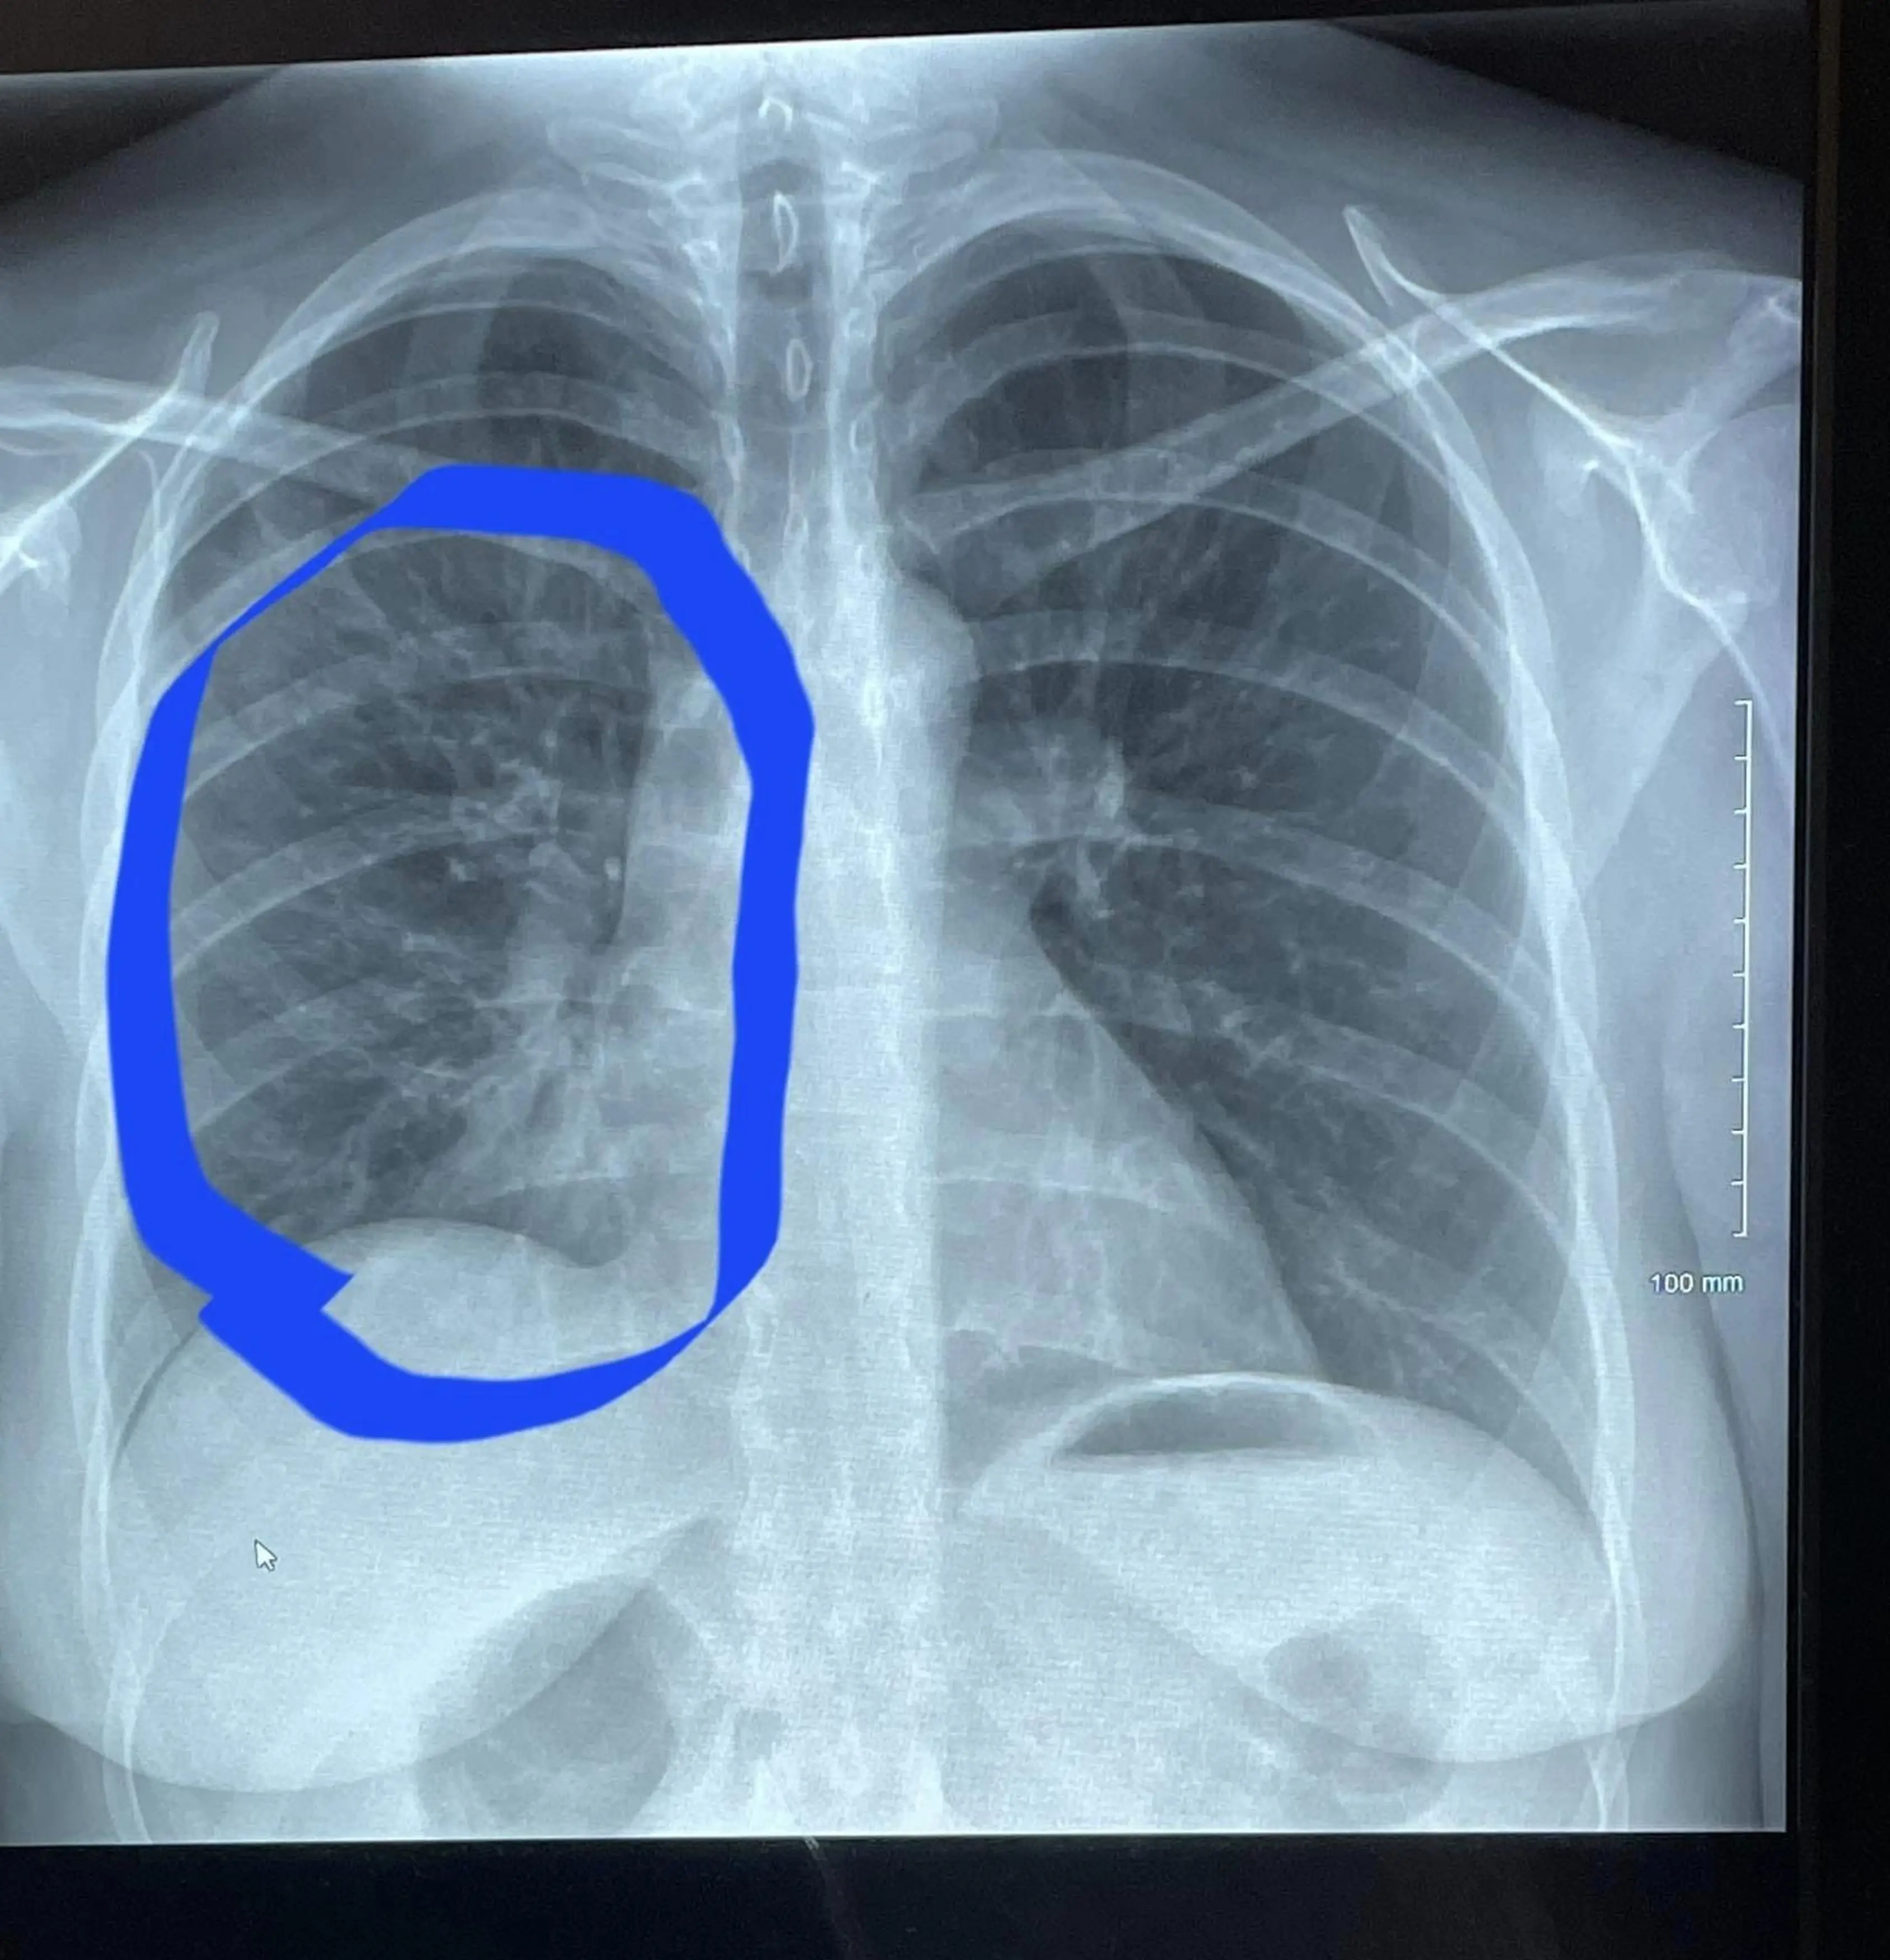

Hannah went to see some more doctors who confirmed she had an obstruction in her right lung.

She continued: "It looks like a tree with branches, it's called 'tree budding' and it's basically the deterioration of your lung.

"It's not supposed to happen unless you're a really heavy smoker."

She said: "I looked like I had the lungs of someone in their 80s, someone much older, when he showed me that first scan.